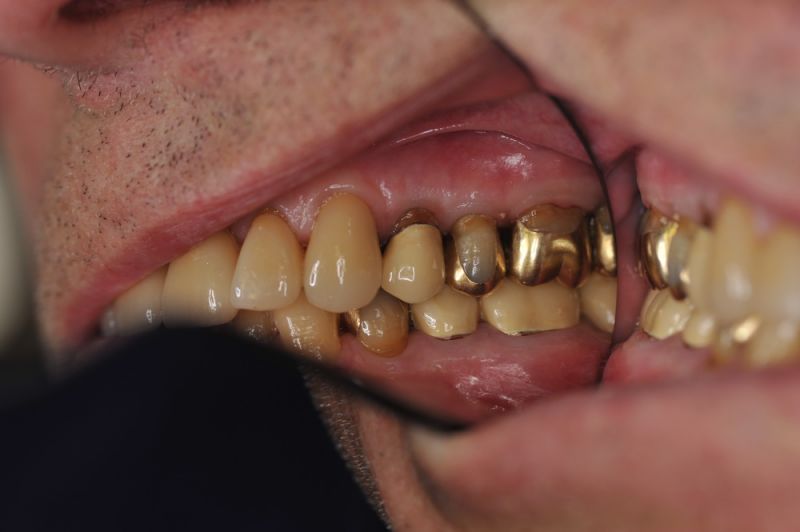

Rekonstruierter Kieler Patient im Recall

Die funktionstherapeutische Rekonstruktion befindet sich seit 17 Jahren im Munde des Patienten.